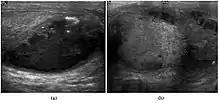

Fig. 3. Seminoma. (a) Seminoma usually presents as a homogeneous hypoechoic nodule confined within the tunica albuginea. (b) Sonography shows a large heterogeneous mass occupying nearly the whole testis but still confined within the tunica albuginea, it is rare for seminoma to invade to peritesticular structures.

Approximately 95% of malignant testicular tumors are germ cell tumors, of which seminoma is the most common. It accounts for 35%–50% of all germ cell tumors. Seminomas occur in a slightly older age group when compared with other nonseminomatous tumor, with a peak incidence in the forth and fifth decades. They are less aggressive than other testicular tumors and usually confined within the tunica albuginea at presentation. Seminomas are associated with the best prognosis of the germ cell tumors because of their high sensitivity to radiation and chemotherapy.

Seminoma is the most common tumor type in cryptorchid testes. The risk of developing a seminoma is increased in patients with cryptorchidism, even after orchiopexy. There is an increased incidence of malignancy developing in the contralateral testis too, hence sonography is sometimes used to screen for an occult tumor in the remaining testis. On US images, seminomas are generally uniformly hypoechoic, larger tumors may be more heterogeneous [Fig. 3]. Seminomas are usually confined by the tunica albuginea and rarely extend to peritesticular structures. Lymphatic spread to retroperitoneal lymph nodes and hematogenous metastases to lung, brain, or both are evident in about 25% of patients at the time of presentation.